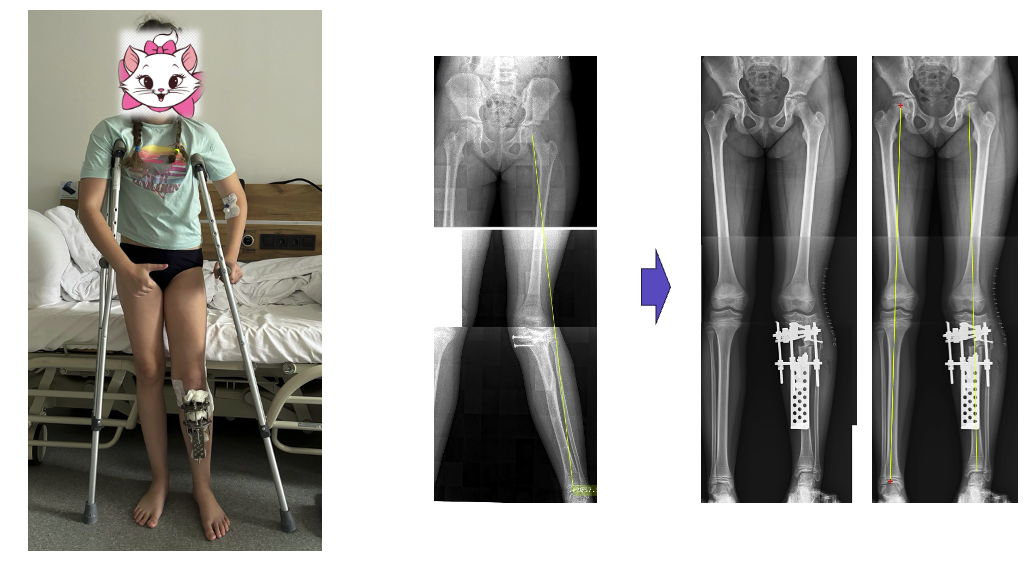

Результат: рівніша хода вже в першу добу

У результаті хірургічного втручання вдалося повністю усунути всі основні компоненти деформації кінцівки. Вісь гомілки була відновлена, перекос тазу значно зменшився, умови для формування вторинного сколіозу усунені. Уже на першу добу після операції пацієнтка змогла самостійно пересуватися з повною опорою на прооперовану ногу за допомогою милиць, що є важливим фактором для ранньої реабілітації та психологічного комфорту дитини.

Повна корекція деформації дозволила зменшити вкорочення кінцівки вдвічі – з 4 до 2 см. Залишкову різницю довжини планується усунути в апараті шляхом контрольованого дозованого подовження гомілки. Це дасть змогу досягти симетрії нижніх кінцівок, покращити ходу, знизити навантаження на хребет і суглоби та повернути дитині можливість жити активним життям без болю.